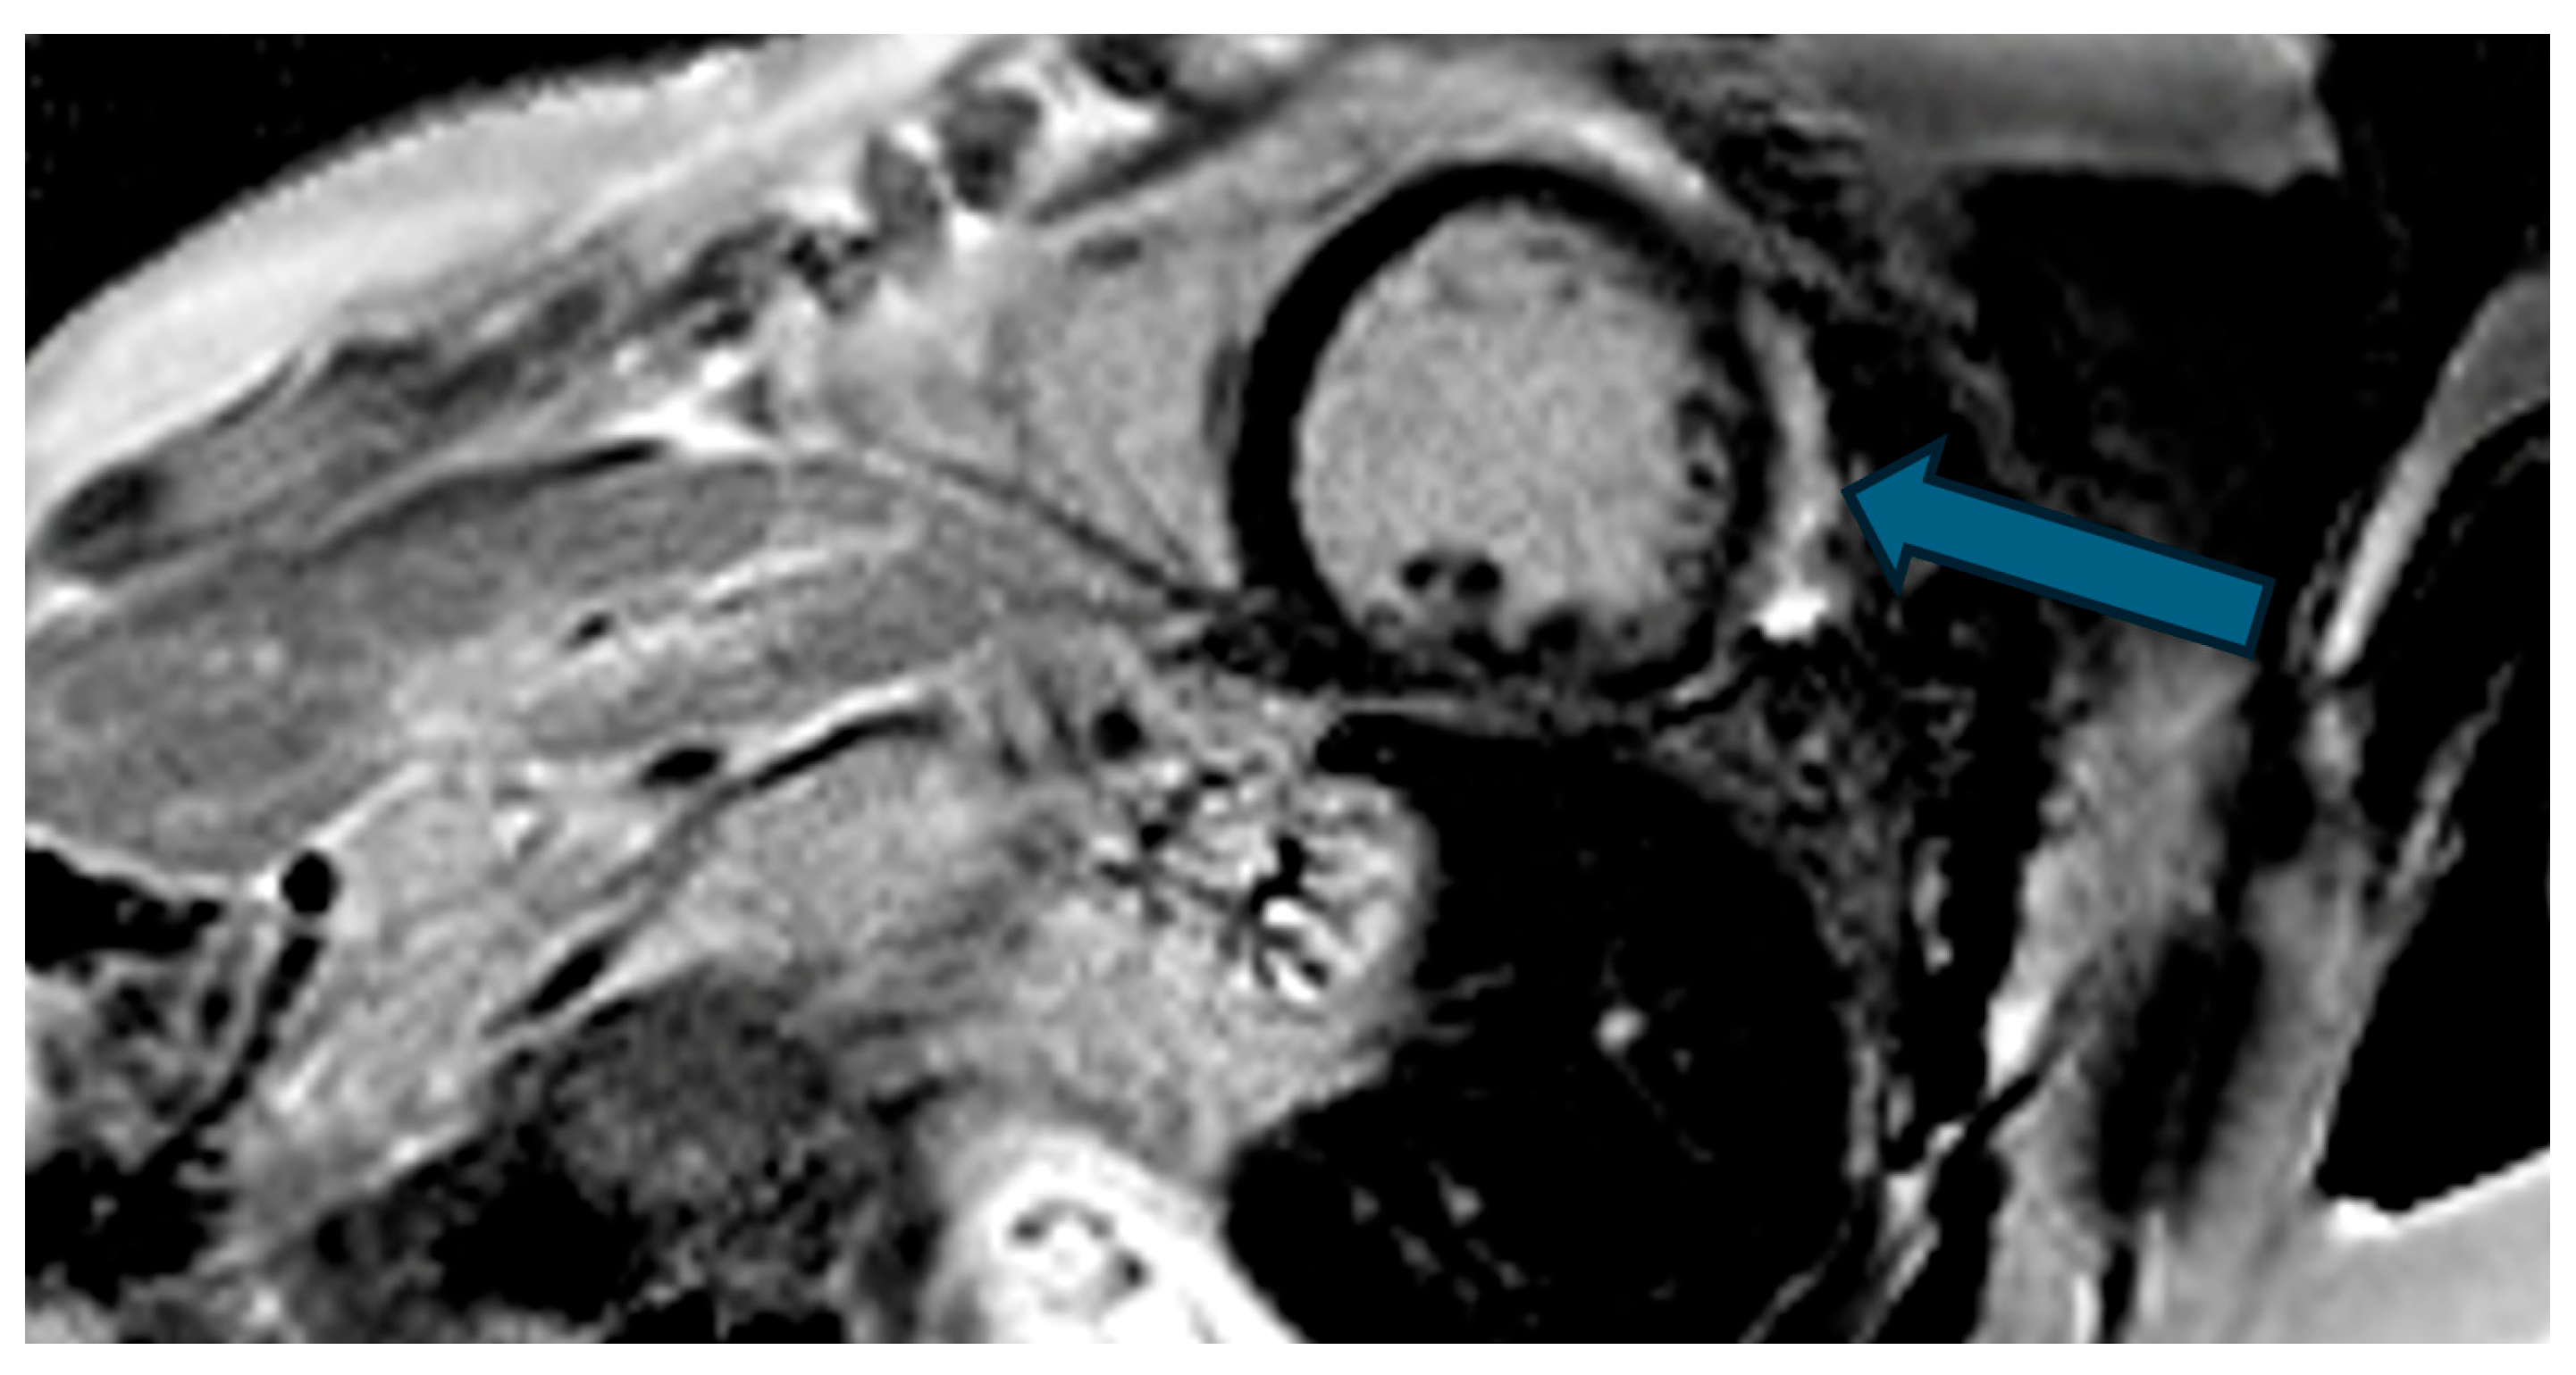

| Case | Patient (Sex, Age) | Symptoms | MAD (mm) | Valvular Issues | LGE | Other Details |

|---|---|---|---|---|---|---|

| 7 | Female, 53 years old | Extrasystole and syncope | 15 | MVP, valvular regurgitation | Basal-lateral | Extensive MAD with MVP and LGE; increased arrhythmic risk; antiarrhythmic therapy considered. |

| 8 | Female, 63 years old | Aortic and mitral regurgitation | 11 | Aortic and mitral regurgitation | Lateral | Aorto-mitral regurgitation with septal hypokinesia; mitral valve repair performed; heart failure therapy started. |